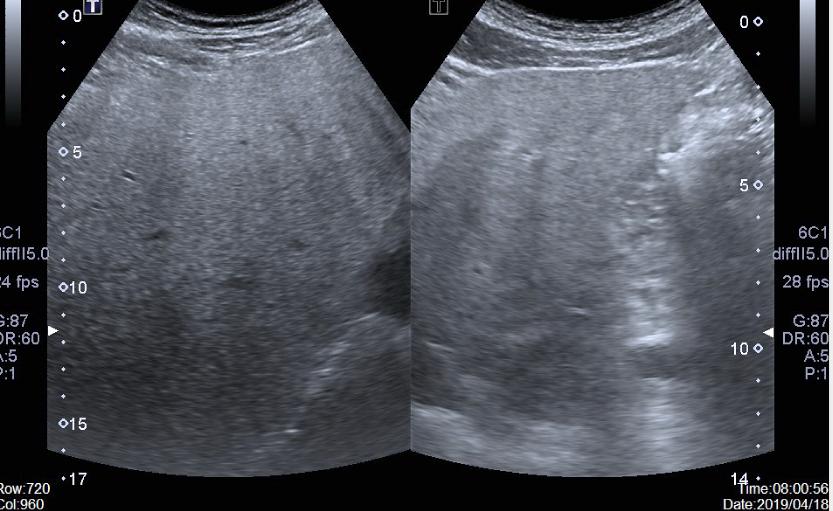

脂肪肝